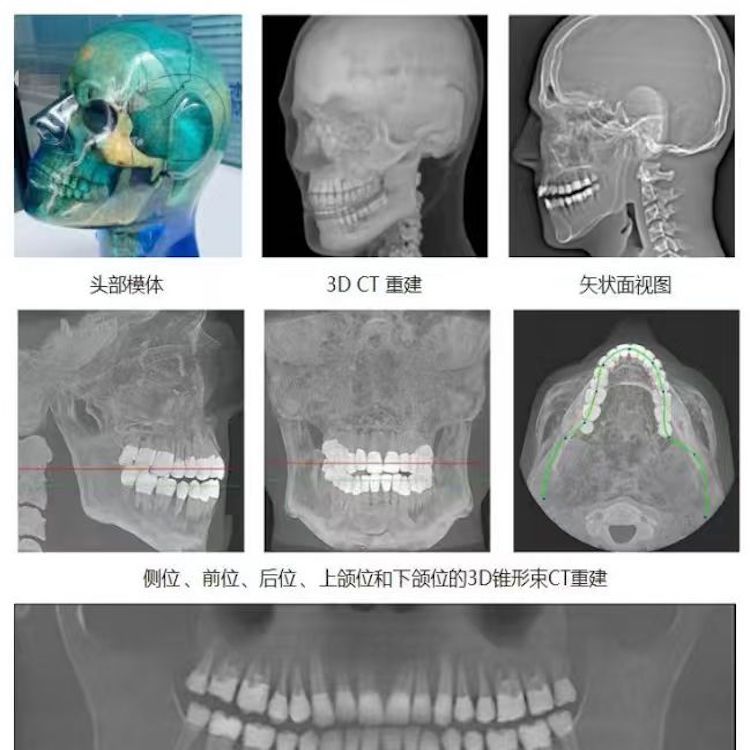

頭部模體是頭部診斷放射學(xué)的參考標(biāo)準(zhǔn),該模體旨在協(xié)助技術(shù)和臨床人員,在大多數(shù)需要精細(xì)解剖細(xì)節(jié)的放射學(xué)程序中選擇、監(jiān)測、培訓(xùn)和驗(yàn)證掃描參數(shù)。 模體為研究人員、臨床醫(yī)生和技術(shù)人員提供了一致性的工具。它非常適合確定最佳系統(tǒng)設(shè)置、調(diào)試新設(shè)備、監(jiān)測系統(tǒng)性能和培訓(xùn)牙科X射線、全景X射線、CT和錐束CT程序。 這個(gè)模體包括一個(gè)可調(diào)節(jié)的支架,用于在錐束 CT 或全景X射線系統(tǒng)中定位。模體的下頜略微張開,前牙垂直排列,以復(fù)制正確的咬合引導(dǎo)定位 。 請注意,實(shí)際咬合引導(dǎo)無法在這個(gè)產(chǎn)品中定位。 頭部模體是由專有組織等效材料制成的。由組織模擬樹脂制成,這些樹脂模擬X射線對人體的衰減特性,適用于CT和治療能量范圍(50keV-25MeV)。 模體在大小和結(jié)構(gòu)上都近似于平均男性頭部 。該模體包括詳細(xì)的3D擬人化解剖結(jié)構(gòu), 包括大腦、骨骼、喉、氣管、鼻竇、鼻腔和牙齒。骨骼包括皮質(zhì)和骨小梁的分離。牙齒包括明顯的牙本質(zhì)、牙釉質(zhì)和包括神經(jīng)的牙根結(jié)構(gòu)。鼻竇完全張開。

頭部模體特點(diǎn) 1. 詳細(xì)的解剖特征; 2. 確定法蘭克福平面以確保正確對齊; 3. 50 keV 至 25 Mev 的組織等效值; 4. 具有六個(gè)自由度的定位支架; 5. 包括泡沫內(nèi)襯手提箱; 6. 12個(gè)月保修。

功能和應(yīng)用 1. X射線 ,全景X射線 ,CT和錐束CT系統(tǒng); 2. 學(xué)習(xí)如何正確定位頭部以獲得最佳圖像; 3. 測試重建技術(shù)和算法 ,用于植入物規(guī)劃和頜面部重建; 4. 在實(shí)施新設(shè)備和新技術(shù)期間培訓(xùn)并評估人員; 5. 驗(yàn)證圖像質(zhì)量的一致性。